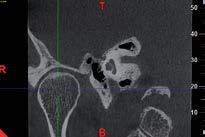

L’innovazione e la sicurezza sono due dei valori perseguiti dallo Studio Braconi a Terni, un punto di riferimento nell’ambito della radiologia 3D ortopedica grazie alla presenza del macchinario Newton 5G XL: si tratta dell’unico apparecchio nel Centro Italia che permette di eseguire una perfetta diagnostica per immagini in ortopedia e per la cervicale, oltre per le piccole articolazioni come seni paranasali, orecchie, colonna cervicale, gomito, polso, mano, ginocchio, caviglia e piede.

Nell’ambito della radiologia 3D ortopedica, il centro diagnostico utilizza il nuovissimo macchinario NewTom 5G XL, in grado di individuare con la massima precisione la presenza di fratture o lussazioni delle articolazioni, controllare la corretta guarigione di una frattura, valutare una lesione o una ferita causata da infezione, artrite o crescita anormale dell’osso.

Un altro valore aggiunto che rende la radiologia 3D ortopedica uno strumento fondamentale nell’ambito della diagnostica per immagini attuale è la bassissima dose di radiazioni emesse: infatti, la tecnologia CBCT garantisce una dose fino a 10 volte inferiore rispetto al MSCT.